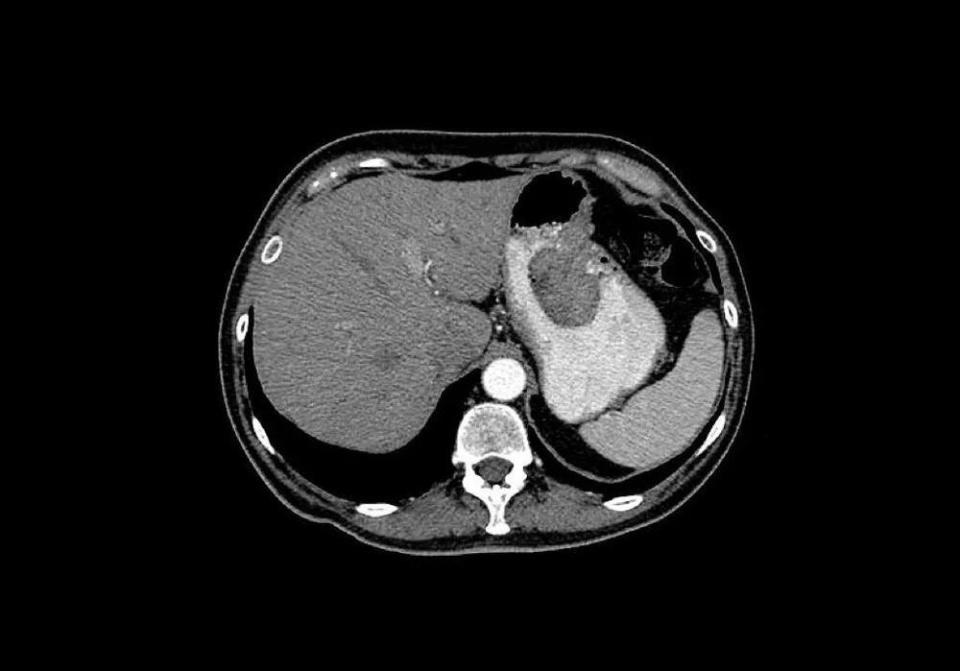

长期摄入过多盐分会破坏胃黏膜屏障,促进异常细胞增殖,增加胃癌风险。

△胃癌CT扫描。

建议限制盐分摄入量,每天不超过5克。同时警惕“隐形盐”,拌饭酱、腐乳、酱油、鸡精、味精、饼干、薯片、话梅、方便面等都是含盐大户。